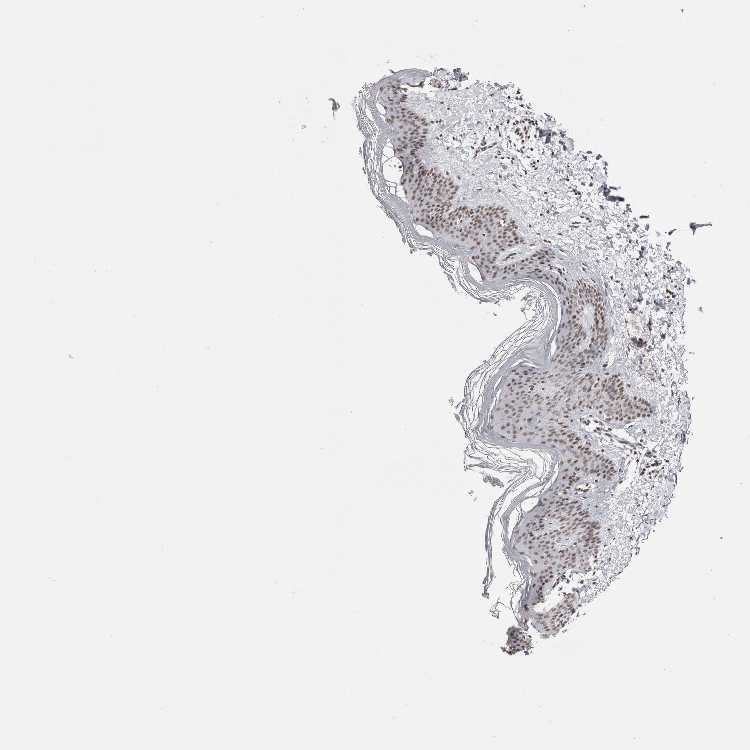

SKIN 2 - Antibody stainingi

Antibody staining in the annotated cell types in the current human tissue is reported as not detected, low, medium, or high, based on conventional immunohistochemistry profiling in selected tissues. This score is based on the combination of the staining intensity and fraction of stained cells.

Each image is clickable and will lead to virtual microscopy that enables deeper exploration of all samples and also displays staining intensity scores, fraction scores and subcellular localization as well as patient and tissue information for each sample.

Antibody CAB025404

Cells in basal layer Medium

Cells in corneal layer Not detected

Cells in granular layer Medium

Cells in spinous layer Medium

Endothelial cells Medium

Extracellular matrix Not detected

Fibrohistiocytic cells Medium

Hair follicles Medium

Langerhans cells Medium

Lymphocytes Medium

Melanocytes High

Vascular mural cells Not detected